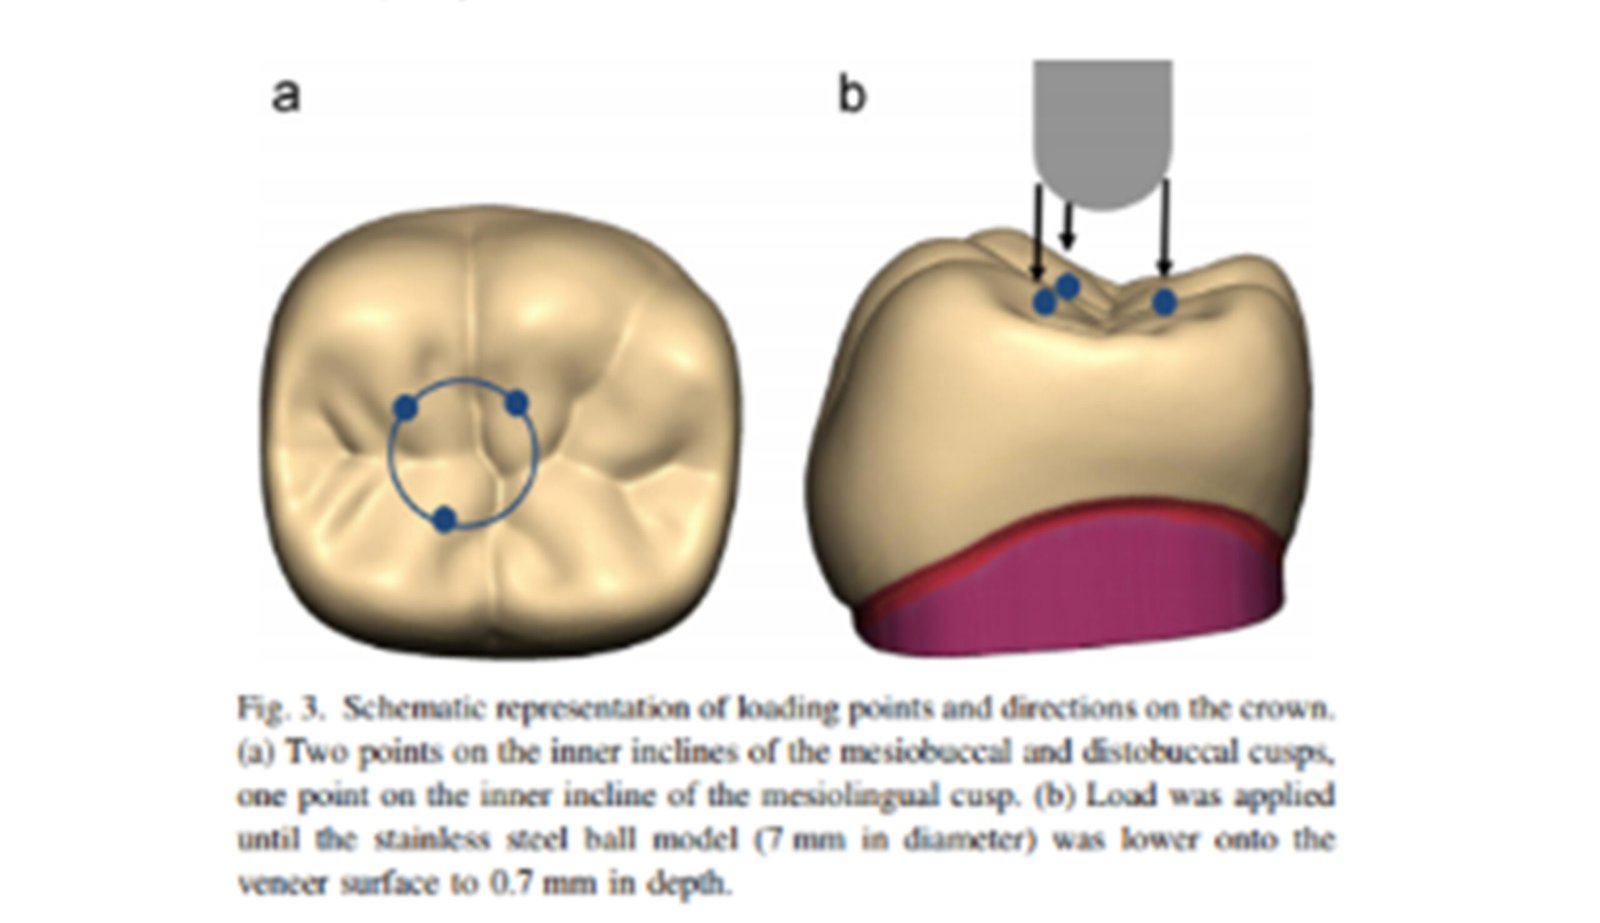

The Endodontic FEA section evaluates the biomechanical performance of root canal–treated teeth, endodontic tools, and reinforcement strategies. Through precise material characterization and micro-CT–based superimposition, we assess fracture risk, stress pathways, and instrument fatigue under various clinical scenarios. These simulations guide the selection of safer instrumentation techniques and restorative strategies. Our goal is to enhance predictability and reduce procedural complications.